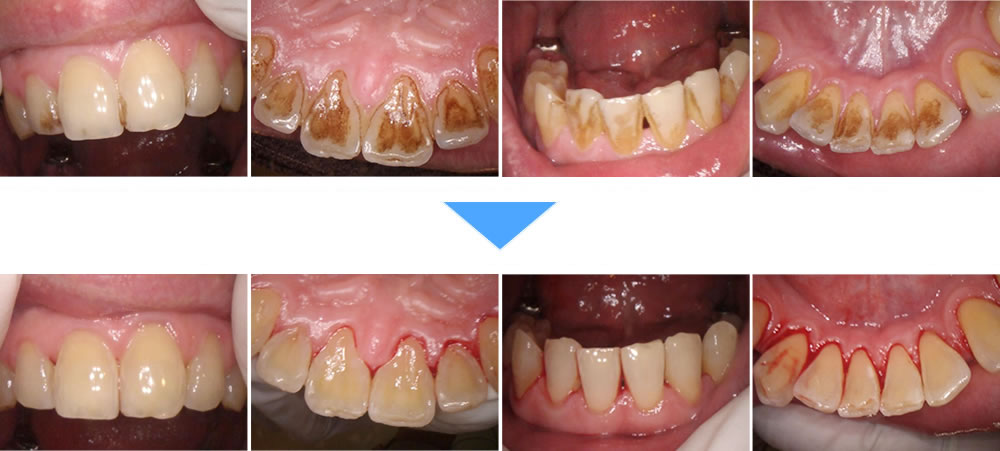

タバコのヤニ・着色汚れをエアフローで改善した症例

年齢

40代

性別

男性

症例を見る

気になる歯の着色汚れをエアフローで除去した症例

30代